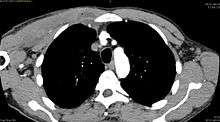

Pyomyositis, also known as tropical pyomyositis or myositis tropicans, is a bacterial infection of the skeletal muscles which results in a pus-filled abscess. Pyomyositis is most common in tropical areas but can also occur in temperate zones.

Pyomyositis is most often caused by the bacterium Staphylococcus aureus.[1] The infection can affect any skeletal muscle, but most often infects the large muscle groups such as the quadriceps or gluteal muscles.[2][3][4]

Pyomyositis is mainly a disease of children and was first described by Scriba in 1885. Most patients are aged 2 to 5 years, but infection may occur in any age group.[5][6] Infection often follows minor trauma and is more common in the tropics, where it accounts for 4% of all hospital admissions. In temperate countries such as the US, pyomyositis was a rare condition (accounting for 1 in 3000 pediatric admissions), but has become more common since the appearance of the USA300 strain of MRSA.[2][3][4]

The abscesses within the muscle must be drained surgically (not all patient require surgery if there is no abscess). Antibiotics are given for a minimum of three weeks to clear the infection.[2]